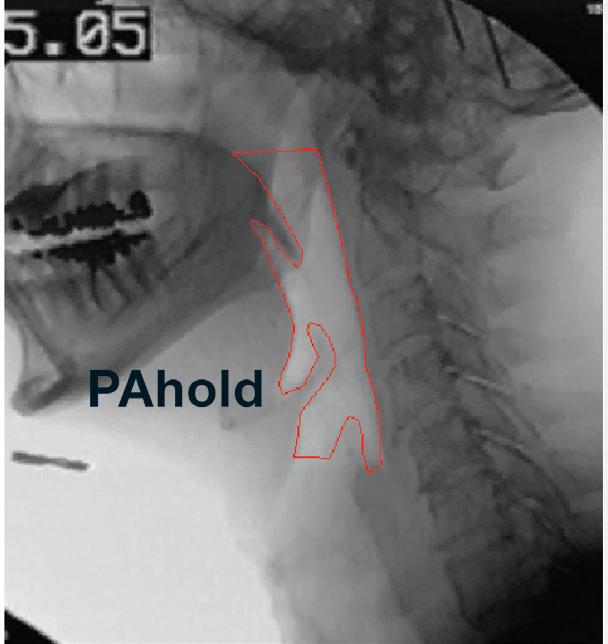

view from videofluoroscopic swallowing study: pharyngeal phase. Note anterior displacement of hyoid and larynx with expansion of the hypopharynx. The tongue base contacts the posterior pharyngeal wall. Subject has a cricopharyngeal bar at cervical vertebra 5.